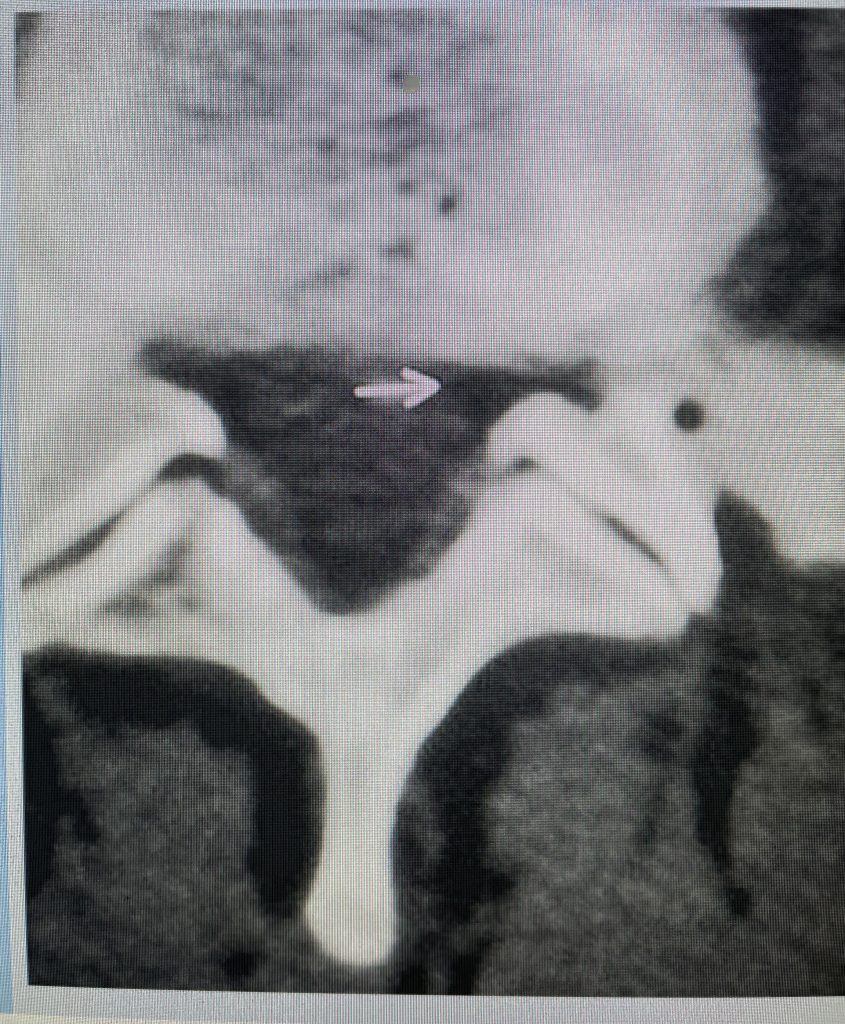

Figure 2: Cartoon axial image of the lumbar spine showing (arrow) severe narrowing of the lateral recess with flattening of the nerve root compared to a normal nerve root on the opposite side.